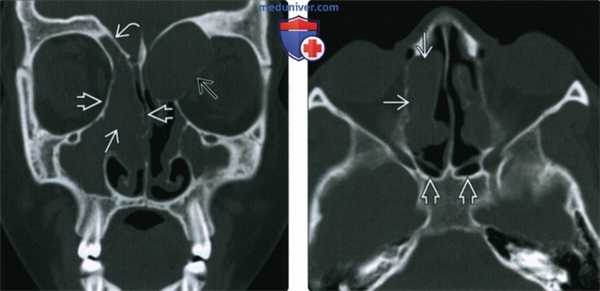

(Слева) При корональной «костной» КТ у девочки 14 лет с муковисцидозом (МВ) определяются типичные признаки ПНП, в т.ч. снижение пневматизации ячеек решетчатой кости справа за счет полиповидного материала, распространяющегося также в полость носа, и доброкачественное ремоделирование костей. Обратите внимание на большое мукоцеле решетчатой кости слева с распространением в орбиту и гипоплазию правой лобной пазухи.

(Справа)При аксиальной «костной» КТ у пациента с МВ визуализируется крупный полип в полости носа справа, связанный со средней носовой раковиной. Выраженная гипоплазия основных пазух часто наблюдается при МВ.